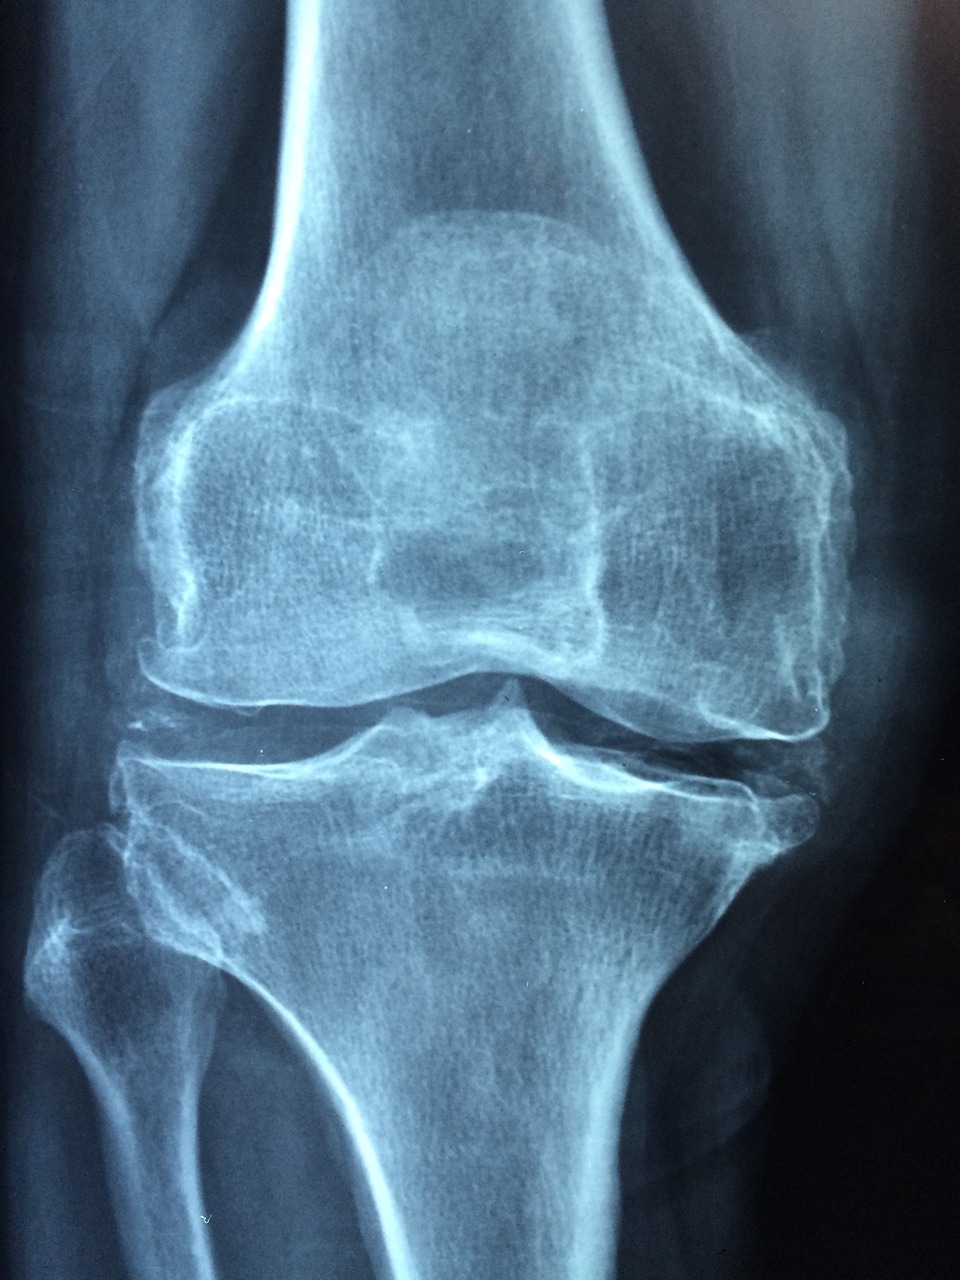

디스크가 신경을 압박하면 다리로 통증이나 저림 무감각이 퍼져나갑니다. 이는 디스크 위치에 따라 다르게 나타나지만 대부분의 허리디스크 환자분들은 다리 및 발에 저림이 있습니다. 해당 증상을 완화하려면 신경을 누르고 있는 디스크에 조치를 해줘야합니다.

특정 신경이 압박받으면 해당 신경이 지배하는 근육의 힘도 같이 약해집니다. 따라서 다리를 들어올리기도 힘들어지며 걷고 뛰는데 어려움을 겪는 경우가 많습니다. 근력 약화까지 진행되었다면 상태가 상당히 심각하다고 볼 수 있으므로 반드시 전문가와의 상담이 필요합니다.

허리디스크가 심해지면 발끝이나 발바닥에 이상한 느낌이 들고 감각이 둔해집니다. 이의 원인은 바로 신경 압박에 의한 것으로 심한 경우엔 발바닥 통증으로 걷는데 지장이 생기는 경우가 있습니다.